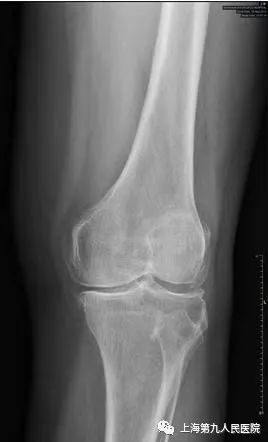

好多膝关节疼痛的朋友到医院寻诊时,医生多会让做一个膝关节的X线检查,就是下方这两张X线片,一张正位片、一张侧位片。

每个人的膝关节是由3块骨头加上一些软骨、韧带等软组织组成的。这3块骨头分别是股骨(大腿骨)、胫骨(小腿骨)和髌骨(膝盖骨)。每块骨头的表面有一层软骨,软骨富有弹性而又光滑,并且没有神经支配,有利于骨头之间无痛而又圆滑的摩擦活动;另外,在股骨和胫骨中间有两个垫片,叫作半月板,有调节冲击力的作用,并让骨表面之间更贴合。在日常生活中,健康的软骨和半月板保证我们的膝关节能够顺畅的完成各种活动。二

全身任何关节都可能发生骨关节炎,由于膝关节使用频繁、活动多、承受体重大等因素,发生骨关节炎更为常见。发生膝骨关节炎的朋友通常表现为关节疼痛、僵硬、肿胀,活动后疼痛加重,休息后有缓解,遇见寒冷、潮湿环境疼痛会加重。有些人平时走路还可以,但是上下台阶、起坐马桶或椅櫈困难;有些人平时疼痛症状轻微,而在一个轻微的扭伤后就出现关节显著的疼痛肿胀,长时间不能缓解。比如,66岁的王阿姨,平时身体没啥毛病,就是左侧膝盖痛了5年多,时好时坏,一开始出现关节疼痛后休息几天就好了,平时也没当回事。后来上下楼梯疼痛明显,平地上也走不远了,还变成了罗圈腿,最近半年关节疼痛更明显,有时晚上睡觉也疼,这样就很少出家门,生活影响很大。1月前到医院检查,拍X线片看到膝关节已经明显退变,缝隙变窄,磨损严重,骨质增生。